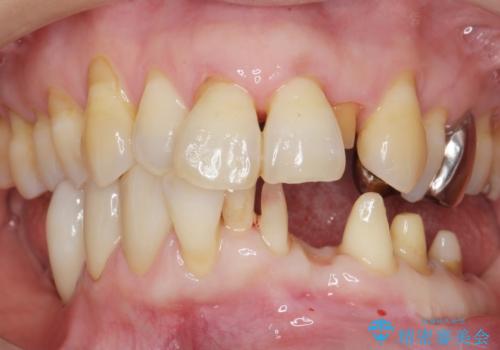

- 下の前歯(左下2)と奥歯の動揺がひどくなってきたことを主訴に来院された患者様です。

精査したところ、前歯の咬み合わせが反対になっていること、下の奥歯(下顎両側67)が4本欠損していることから動揺が生じていました。

矯正治療やインプラント・再生療法を併用した全顎的な治療を提案させて頂いたところ、予算を抑えて早く治したいとのことでご希望されませんでした。

入れ歯も抵抗があるとのことから、相談を重ね、今の状態では保存不可能な下の前歯(左下2)を抜去し、ブリッジや連結補綴により動揺を抑えることにしました。

また、咬み合わせが反対になっている上の前歯(左上2)も補綴で形を変えることにより、咬合を改善しました。